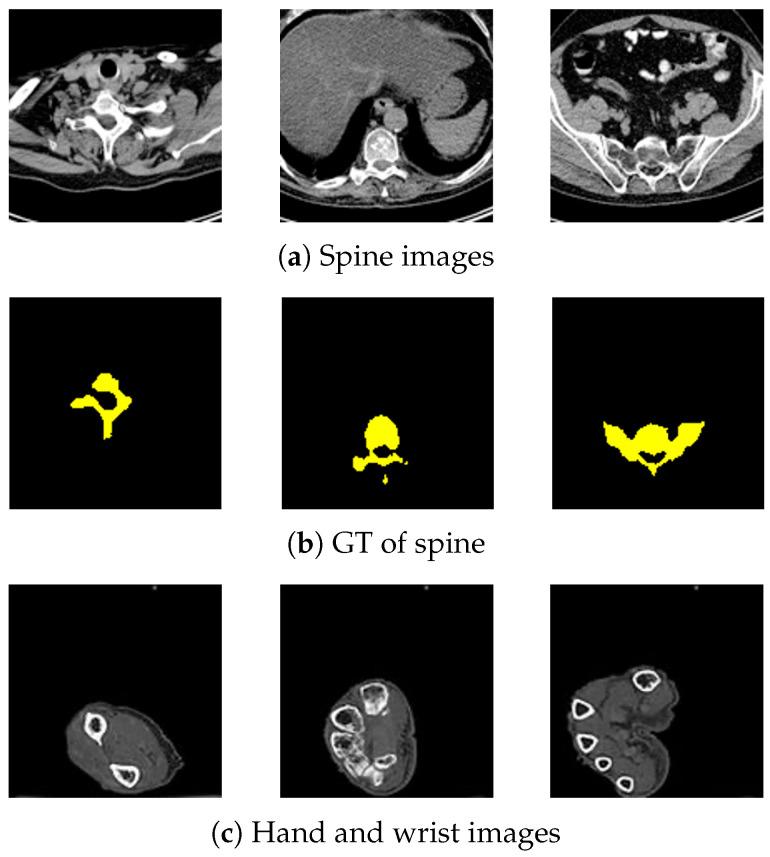

The semantic segmentation of bone structures demands pixel-level classification accuracy to create reliable bone models for diagnosis. While Convolutional Neural Networks (CNNs) are commonly used for segmentation, they often struggle with complex shapes due to their focus on texture features and limited ability to incorporate positional information. As orthopedic surgery increasingly requires precise automatic diagnosis, we explored SegFormer, an enhanced Vision Transformer model that better handles spatial awareness in segmentation tasks. However, SegFormer's effectiveness is typically limited by its need for extensive training data, which is particularly challenging in medical imaging, where obtaining labeled ground truths (GTs) is a costly and resource-intensive process. In this paper, we propose two models and their combination to enable accurate feature extraction from smaller datasets by improving SegFormer. Specifically, these include the data-efficient model, which deepens the hierarchical encoder by adding convolution layers to transformer blocks and increases feature map resolution within transformer blocks, and the FPN-based model, which enhances the decoder through a Feature Pyramid Network (FPN) and attention mechanisms. Testing our model on spine images from the Cancer Imaging Archive and our own hand and wrist dataset, ablation studies confirmed that our modifications outperform the original SegFormer, U-Net, and Mask2Former. These enhancements enable better image feature extraction and more precise object contour detection, which is particularly beneficial for medical imaging applications with limited training data.

骨结构的语义分割需要像素级的分类精度,以便创建可靠的骨模型用于诊断。虽然卷积神经网络(CNN)通常用于分割,但由于它们专注于纹理特征且整合位置信息的能力有限,在处理复杂形状时往往存在困难。随着骨科手术对精确自动诊断的需求日益增加,我们探索了SegFormer,这是一种增强的视觉Transformer模型,能在分割任务中更好地处理空间感知。然而,SegFormer的有效性通常受到其对大量训练数据需求的限制,这在医学成像中尤其具有挑战性,因为获取带标注的真实数据(GT)是一个成本高昂且资源密集的过程。在本文中,我们提出了两种模型及其组合,通过改进SegFormer,能够从较小的数据集中进行准确的特征提取。具体来说,这些包括数据高效模型,它通过在Transformer块中添加卷积层来加深层次编码器,并提高Transformer块内的特征图分辨率;以及基于特征金字塔网络(FPN)的模型,它通过特征金字塔网络(FPN)和注意力机制来增强解码器。在来自癌症成像存档的脊柱图像以及我们自己的手部和腕部数据集上测试我们的模型,消融研究证实我们的改进优于原始的SegFormer、U-Net和Mask2Former。这些增强功能能够实现更好的图像特征提取和更精确的对象轮廓检测,这对于训练数据有限的医学成像应用特别有益。